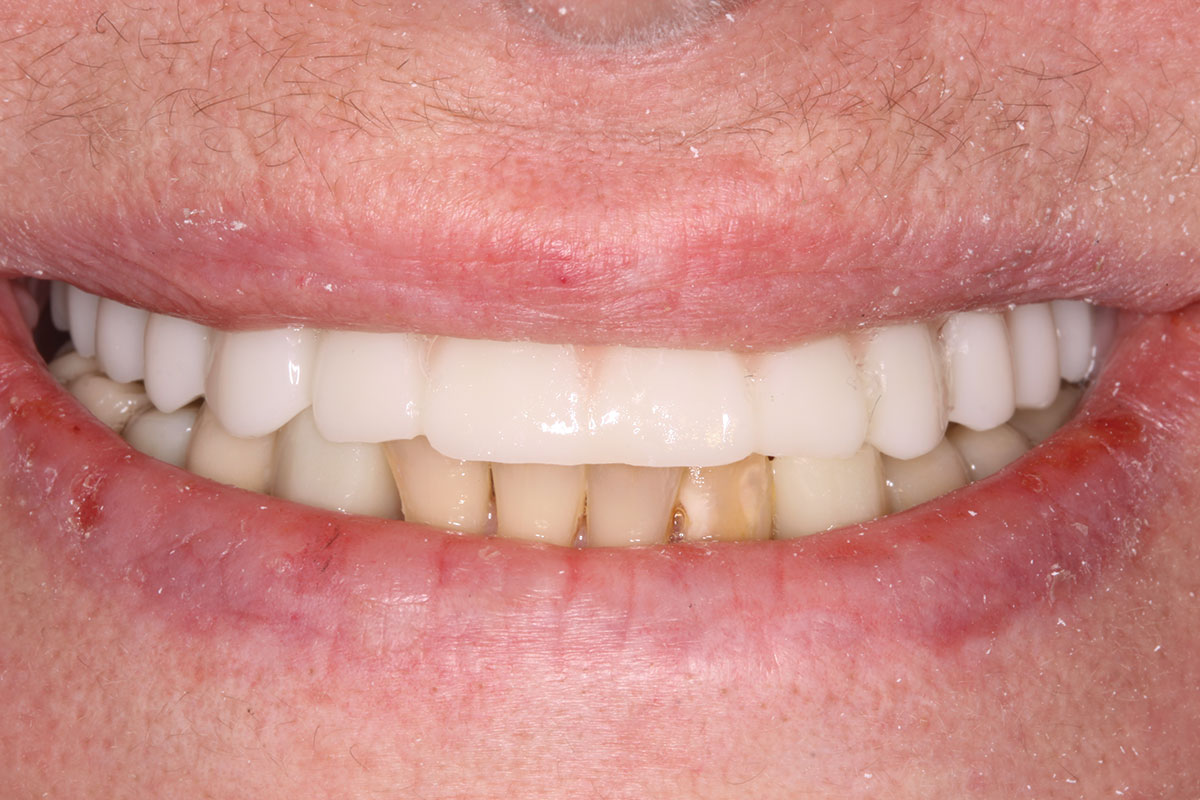

Fig 9. Case 2: Initial presentation for maxillary immediate implant, immediate load provisional restoration. Full-face photograph.

Figure 9

Fig 18. Implants and provisional maxillary prosthesis in place, the same day as surgery.

Figure 18

Fig 19. The patient’s smile display, the same day as surgery.

Figure 19